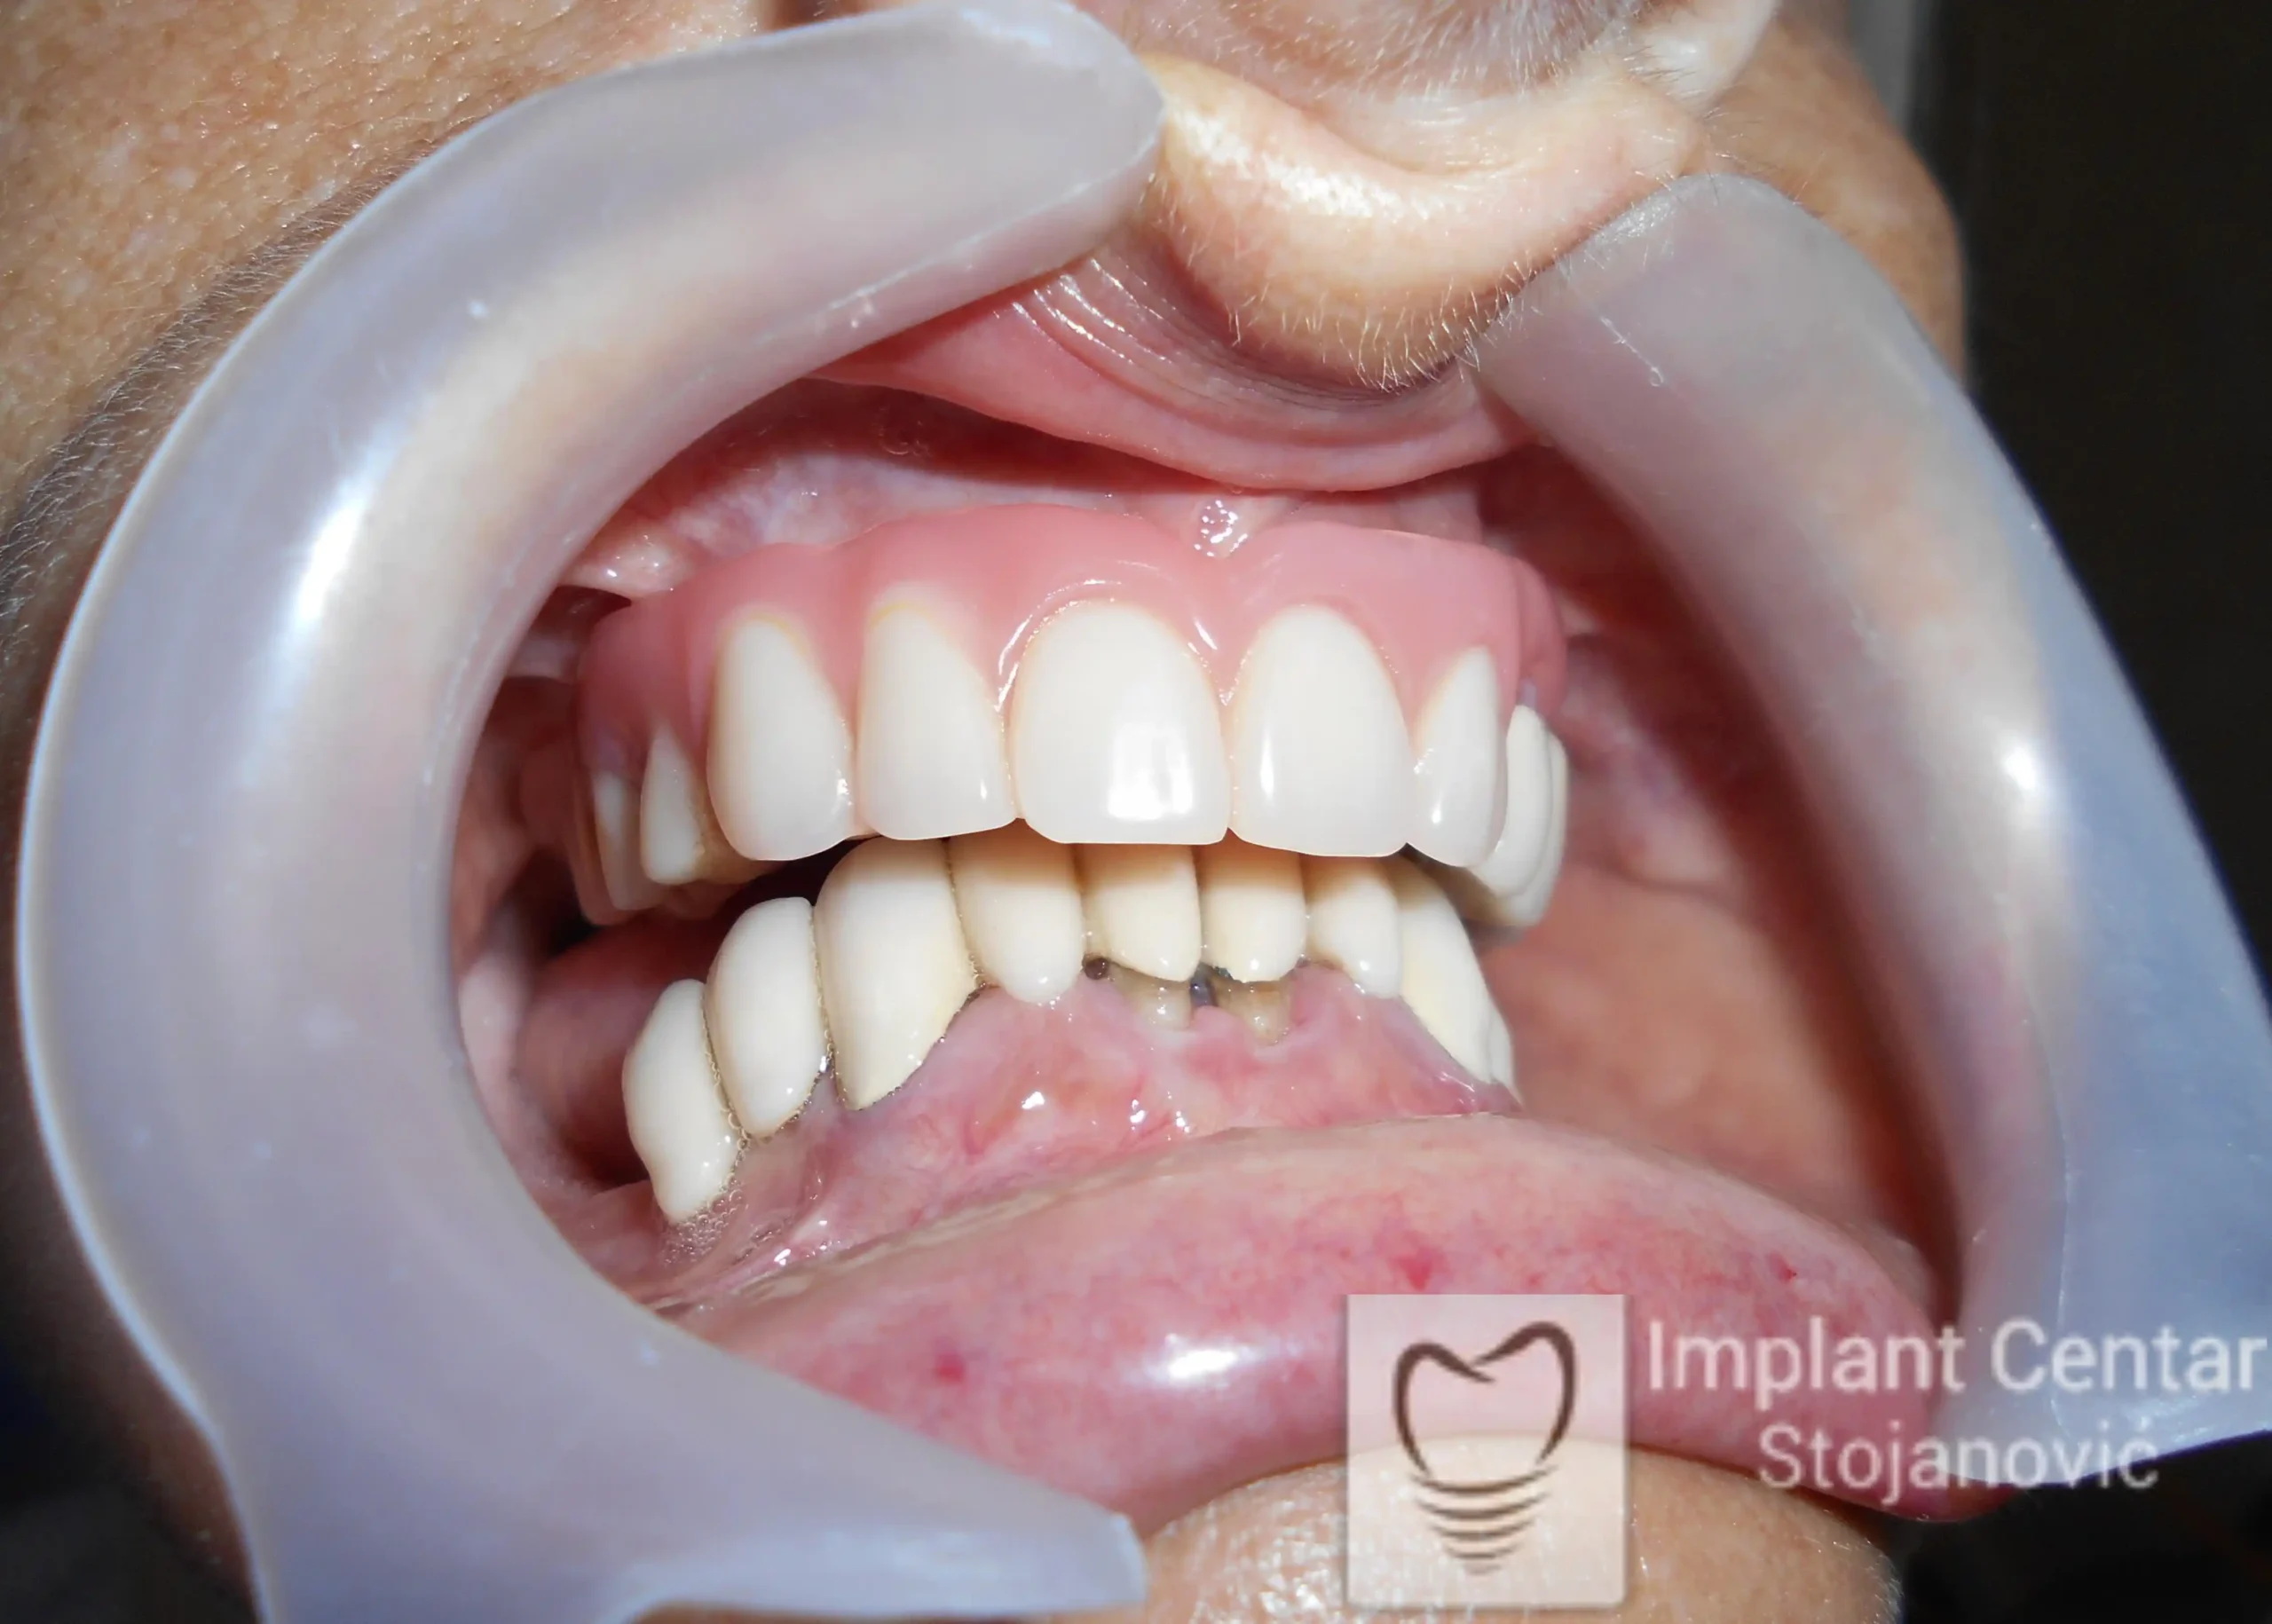

Nakon detaljnog kliničkog pregleda i analize radioloških snimaka, doneta je odluka o vađenju svih zuba u gornjoj vilici, koji su potom zamenjeni dentalnim implantatima. U posteriornim regijama gornje vilice ugrađena su dva tuberopterigoidna implantata, čime je izbegnuta sinus lift procedura.

U donjoj vilici sprovedena je kombinovana rehabilitacija, uz očuvanje prirodnih zuba i ugradnju implantata u bezube prostore. Tokom perioda zarastanja, pacijent je već dva dana nakon hirurške intervencije bio zbrinut fiksnim privremenim krunicama, čime su odmah obezbeđeni funkcija i estetika.

Nakon završetka perioda oseointegracije, izrađen je definitivni protetski rad od cirkonijum-keramike. Pacijent je izrazio visok stepen zadovoljstva postignutim funkcionalnim i estetskim rezultatom.